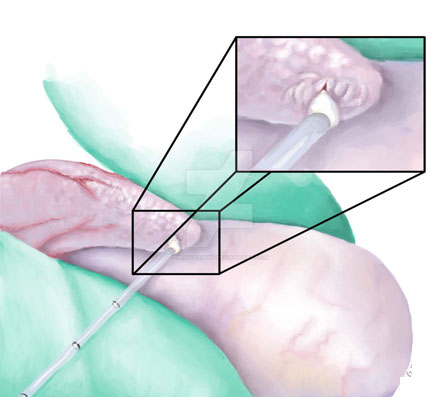

• Micro TESE is a procedure performed for men who have a sperm production problem and Azoospermic

• Micro TESE is performed in the operating room with the General anesthesia under the operating microscope

• Micro TESE is carefully coordinated with the Female Partner's Egg Retrieval, and this procedure is performed the day before Egg Retrieval

• This allows each partner to be there for the other's procedure. Patients frequently have Sonor Sperm backup in case Sperms are not found in the Male partner. Micro TESE has significantly improved Sperm Retrieval rates in Azoospermic men

• Micro TESE is a safer procedure, since less testicular tissue is removed

• Patient's Cryopreserve Sperm is retrieved during this procedure for future In Vitro Fertilization (IVF) and Intra-Cytoplasmic Sperm Injection (ICSI)